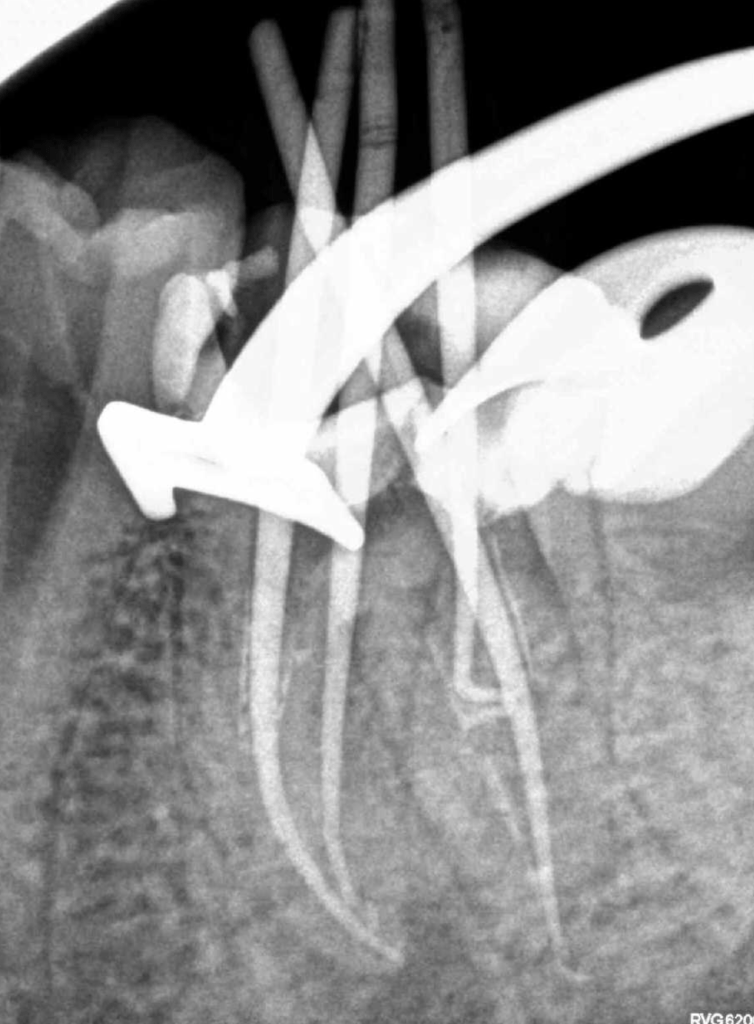

2 Limas rotas + reco Preendo

Lima en conducto MV

Lima rota apical curación un año